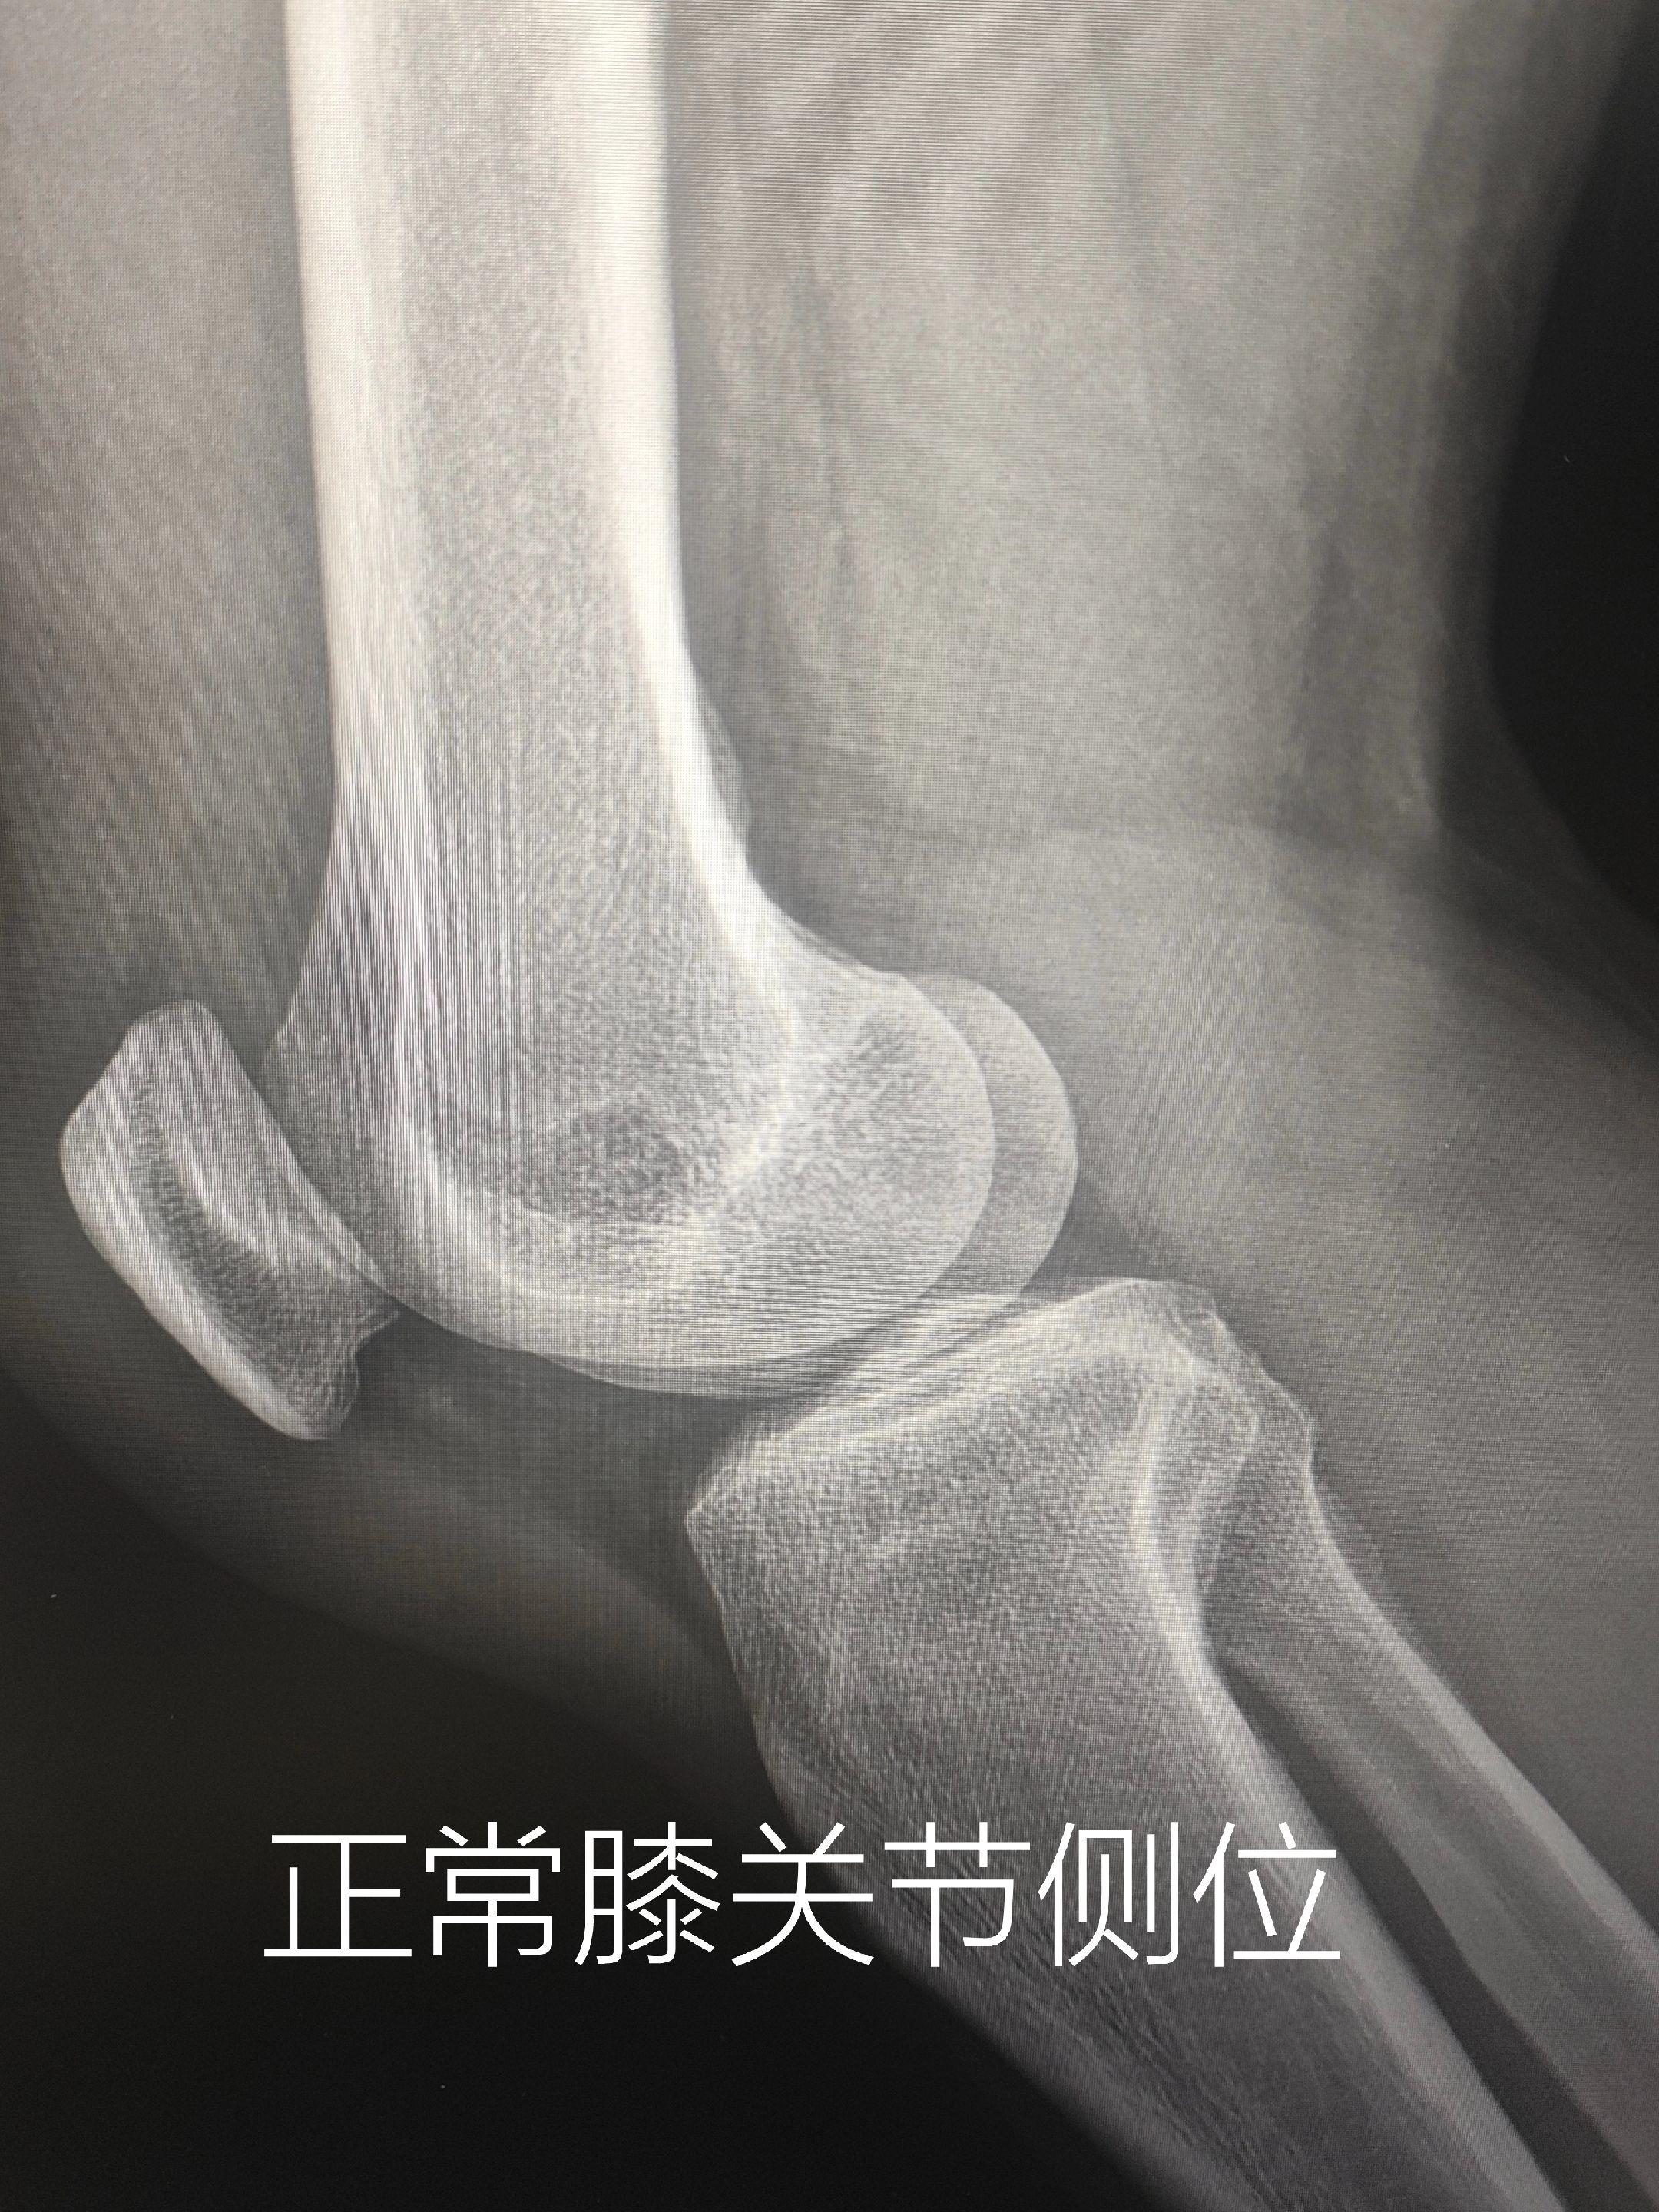

膝关节痛。